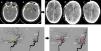

To the best of our knowledge, we report the first case of partial obstruction of a vertebral artery in a patient with COVID-19.

Decompressive surgery remains a life-saving maneuver in these patients (as in other non-COVID-19 strokes) and requires further investigation.